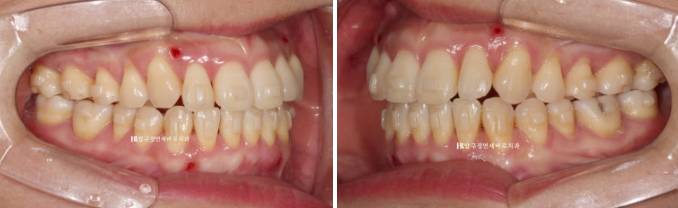

선수술로 양악수술을 한 뒤에 한달 후 내원했을 때의 사진입니다.

23.02

심한 개방교합이 관찰되는 환자분입니다.

수술이 잘못된걸까요?

아닙니다. 물리치료를 하는 기간이라 그렇습니다.

잇몸에 심어진 나사에 고무줄을 걸며 턱 위치를 안정화 시키는 과정이 필요합니다.

IVRO인지 SSRO인지 수술방법에 따라 그리고 수술결과에 따라 이 과정이 몇 달 걸릴 수 있습니다.

턱 위치가 안정이 된 후 교정을 시작하기로 하고 물리치료도 몇 달 더 진행했습니다.